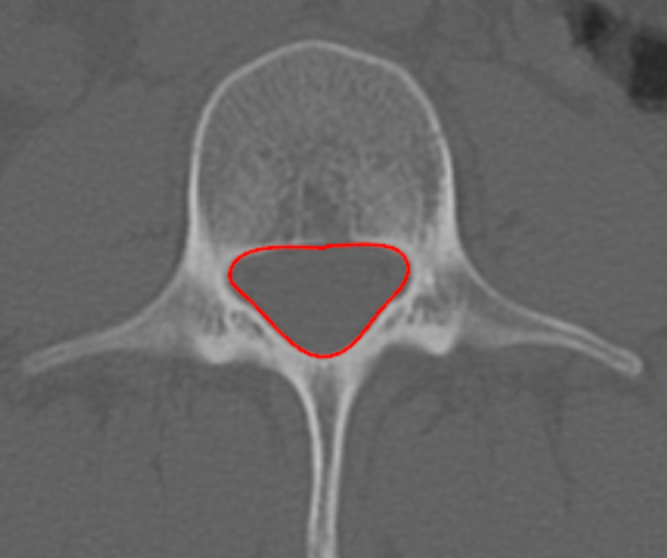

Cross-Sectional Area of Canal (CSA)